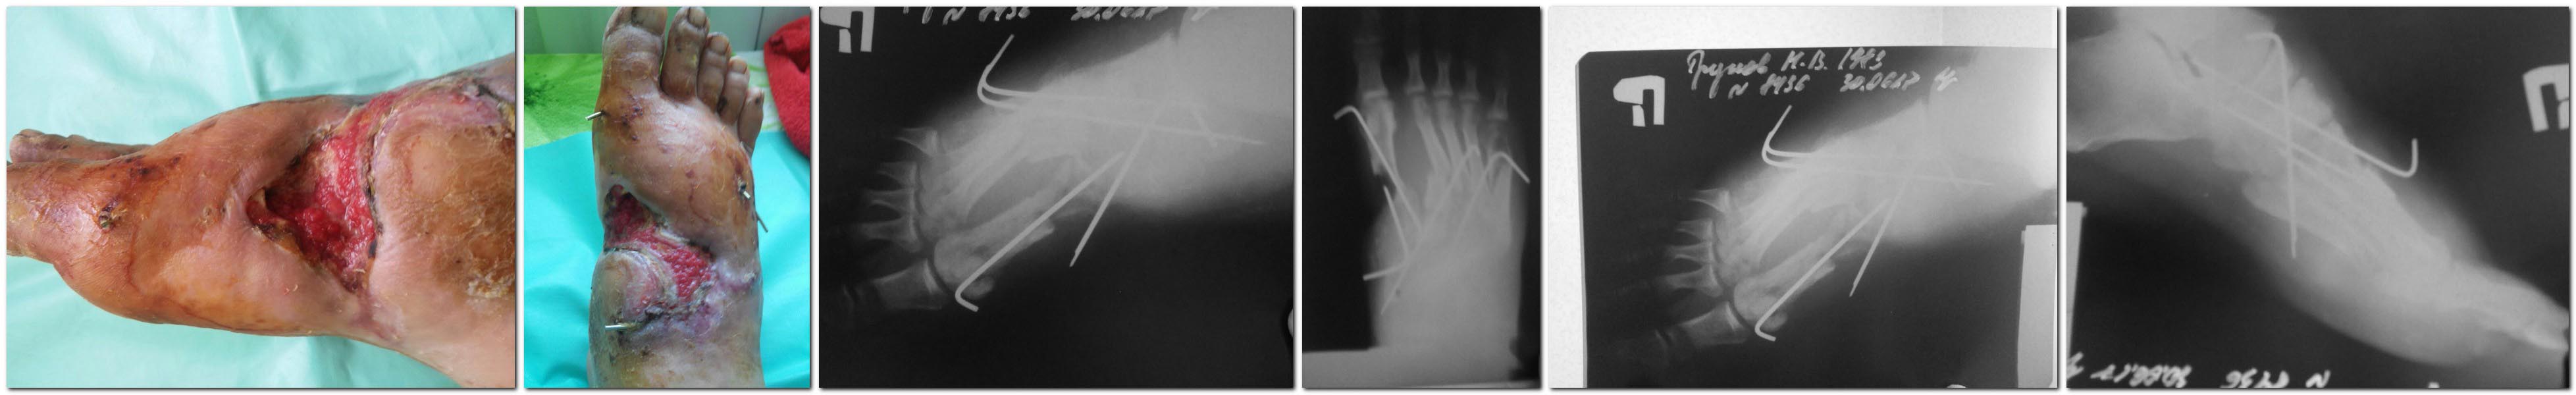

Добрый день , уважаемые коллеги! Интересует ваше мнение относительно

тактики лечения данного повреждения.

Травма 27.04.17.- открытая травма стопы с переломом 1-5 плюсневых костей

и дефектом мягких тканей( со слов принимавшего доктора); выполнена ПХО с

фиксацией спицами. В дальнейшем развились некрозы мягких тканей и

основания 1 - плюсневой кости ( в области перелома),

выполнялись ВХО, перевязки.

На данный момент -картина представлена на фото; в ране отломок 1

плюсневой кости.

Поделитесь, пожалуйста, вашими соображениями по поводу дальнейшего

ведения.Что делать с 1 плюсневой в данном её состоянии? Заранее признателен!